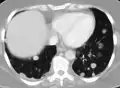

صورة أشعة مقطعية لانبثاث في الرئة

سرطان منتشر في الرئتينMark.png.webp)